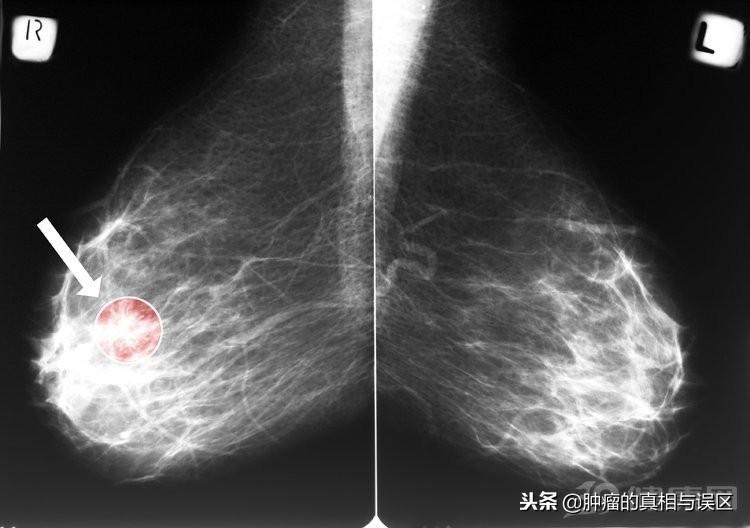

1、乳房肿块

乳房出现肿块是乳腺癌一个很典型的早期症状,大多数的乳腺癌早期都是无痛性的肿块,少数的女性会伴随着隐痛或者是刺痛。对于成年女性来说,当乳房内出现不知名的肿块的时候,一定要引起足够的重视,一般情况下,乳腺癌所出现的肿块都是单个的,只有少部分的女性会出现过个的肿块。